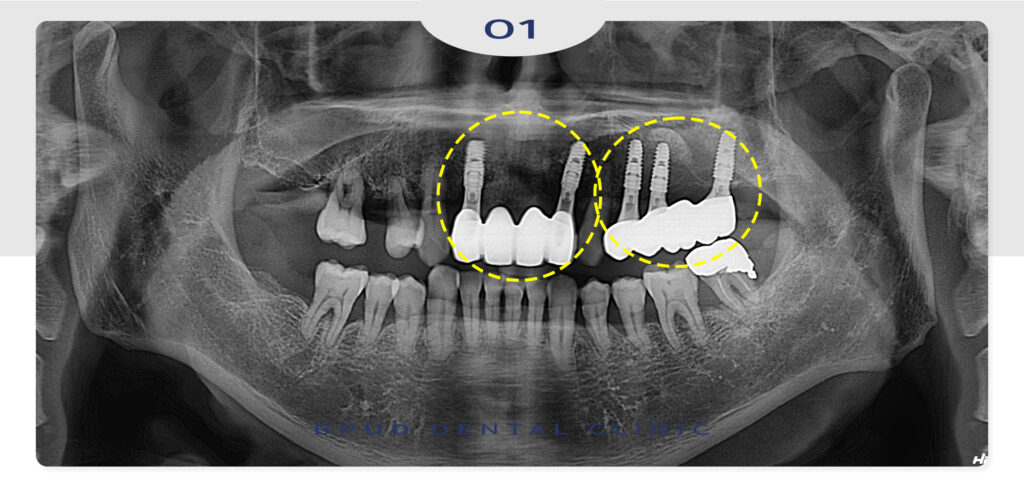

부러진 앞니도 발치 후 양쪽에 2개 임플란트를

식립하여 최종 보철물까지 마무리하였습니다.

환자분께서도 전반적인 치료에 만족 하셨으며

나머지 치료도 모두 진행하시기로 하였답니다!